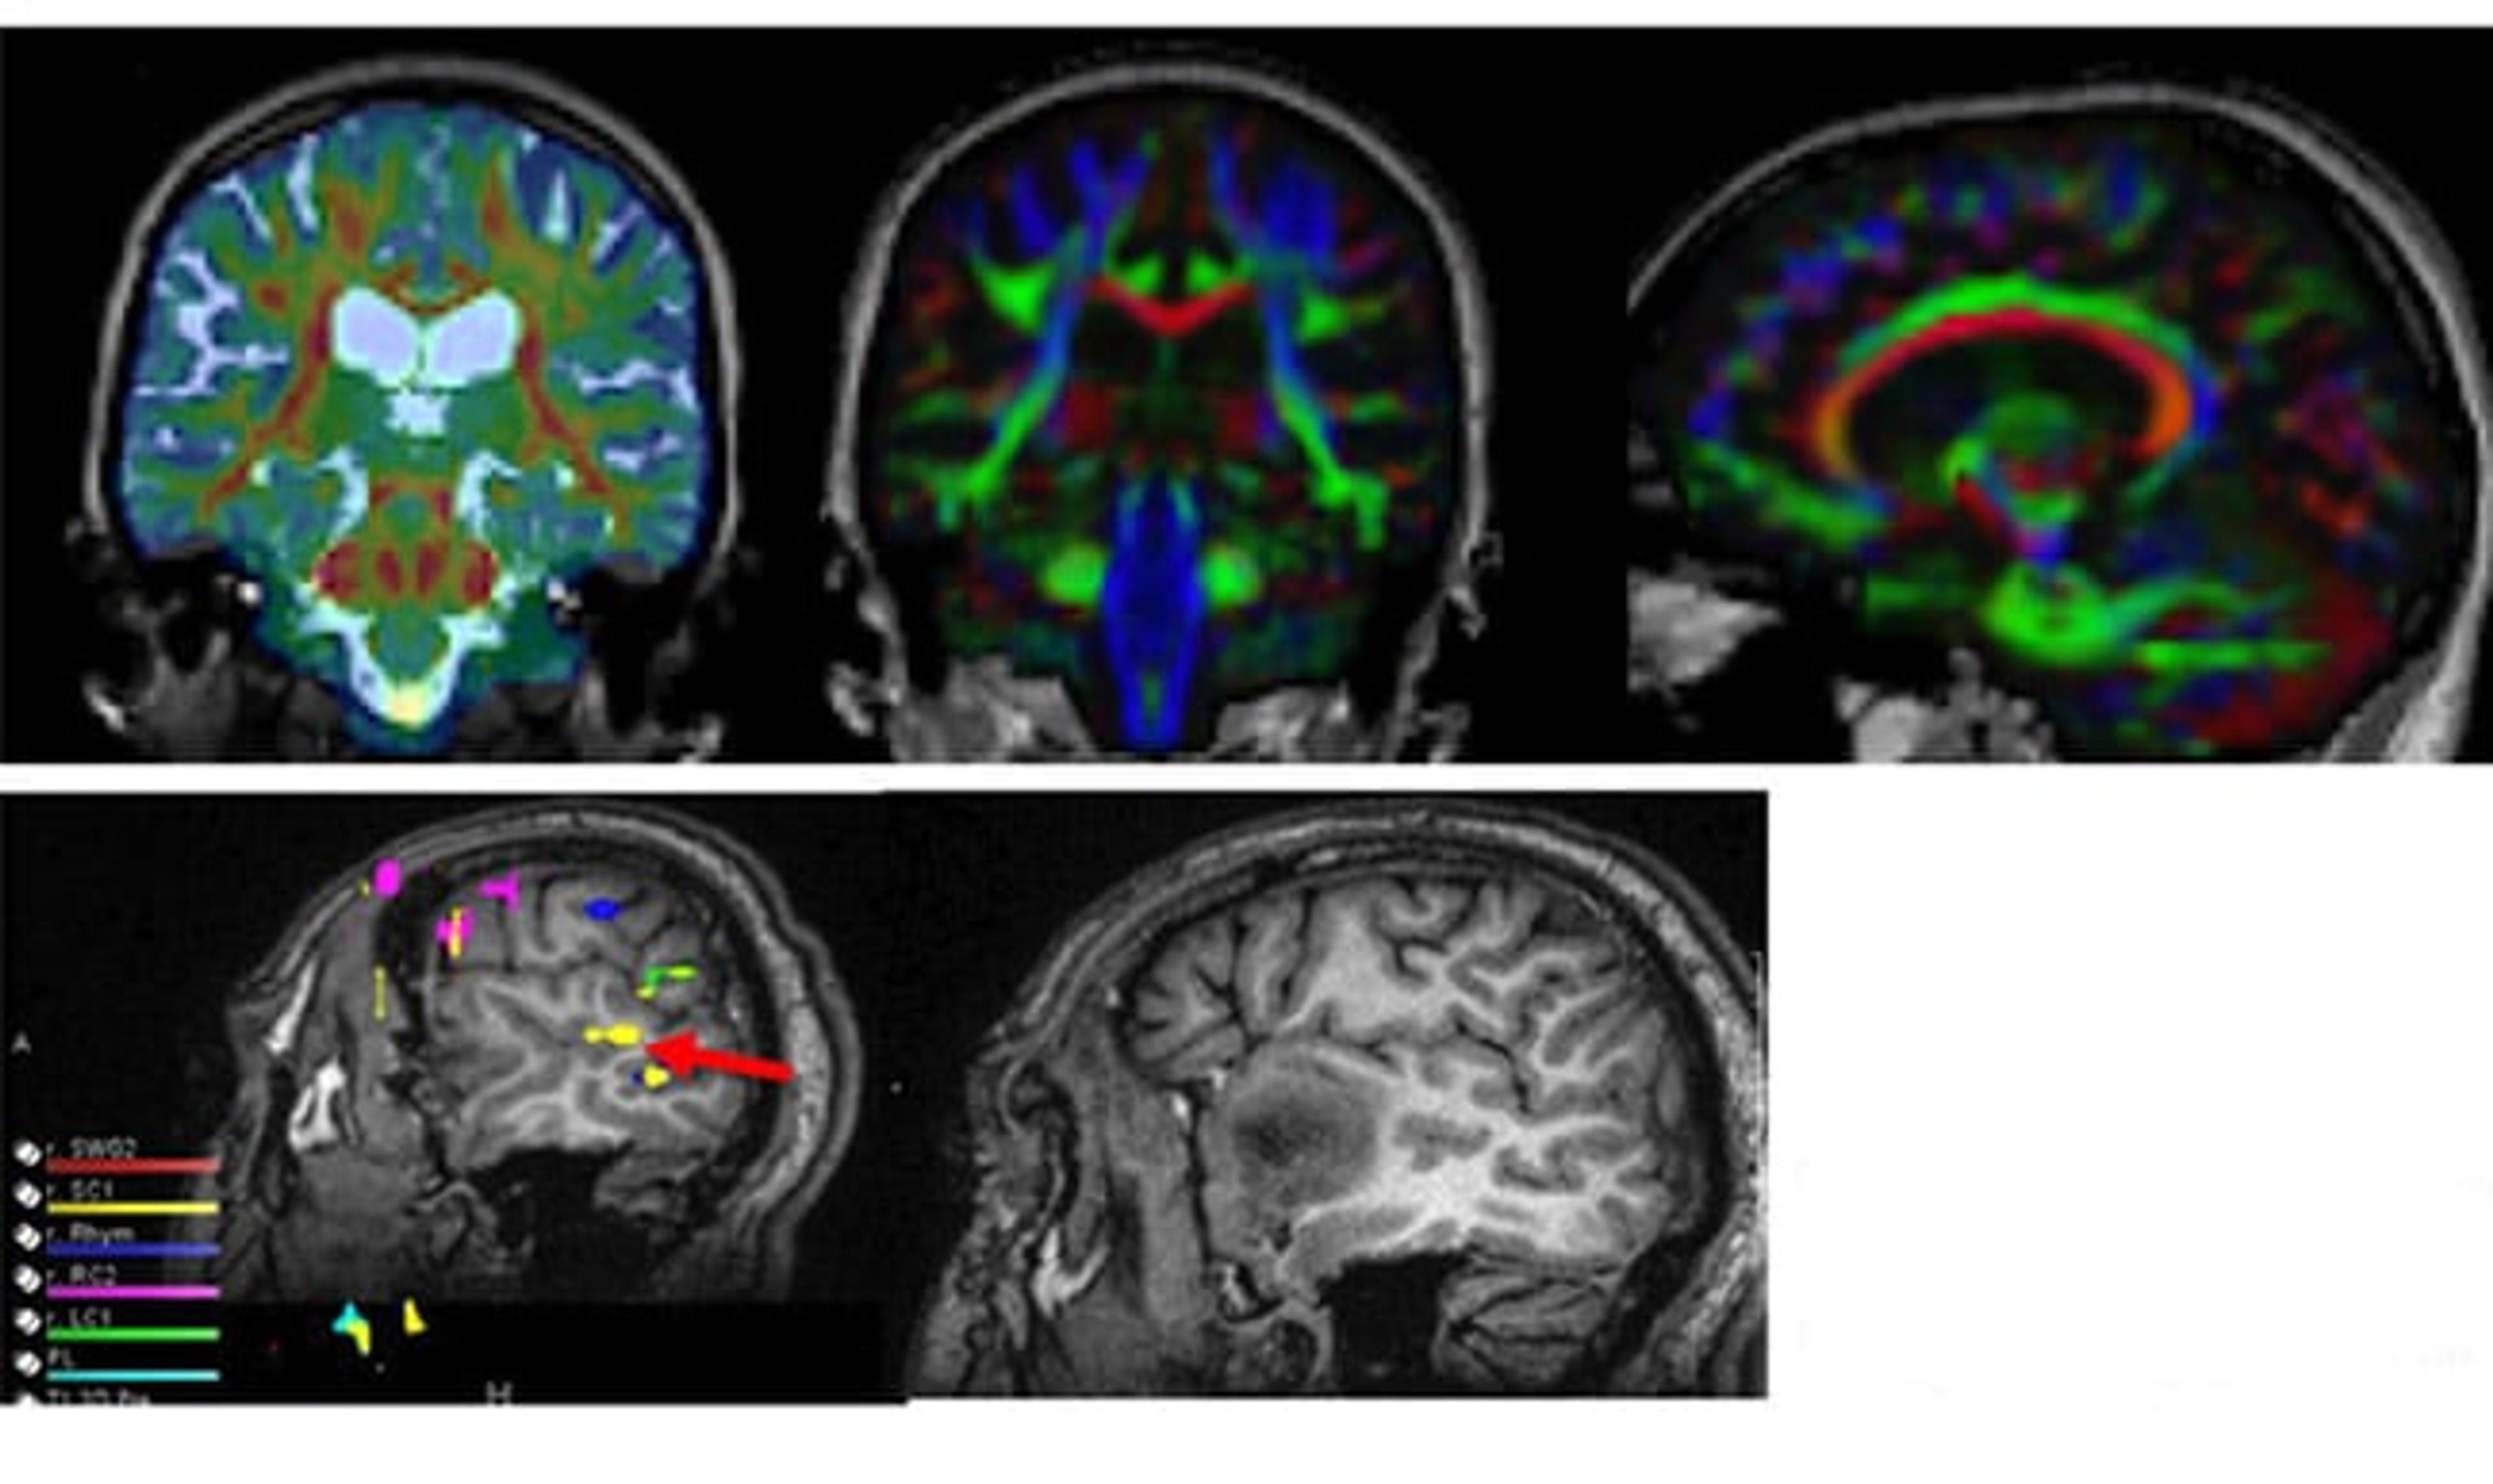

PRISM Imaging - CNS Neoplasms

Delve into the world of central nervous system neoplasms and learn how PRISM Imaging is revolutionizing its diagnosis and treatment.

PRISM Imaging deeply delves into the realm of Central Nervous System (CNS) neoplasms, offering innovative imaging solutions for:

- Tumor Treatment Planning: Utilizing state-of-the-art imaging technology, PRISM aids in the creation of comprehensive treatment strategies. Our goal is to provide insights that could help tailor personalized treatment plans, facilitating better therapeutic decisions.

- Treatment Response Assessment: With the ability to monitor treatment progression, PRISM offers a valuable resource for evaluating the effectiveness of implemented therapies. We aim to track the responsiveness of CNS neoplasms to treatment, potentially providing critical information for adjusting therapeutic approaches when necessary.

Our commitment lies in leveraging cutting-edge imaging technology to assist in the planning and assessment of treatment for CNS neoplasms, contributing to advancements in the care of these complex conditions.